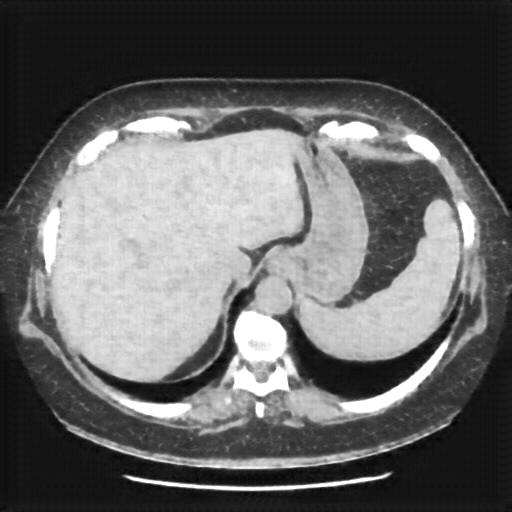

Original NATIVE CT scan (input)

Lung window (WL -600, WW 1500 β†’ Low βˆ’1350, High +150)

Reconstructed NATIVE CT scan (cycle consistency)

Original VENOUS CT scan

Generated VENOUS CT scan (A→B translation)